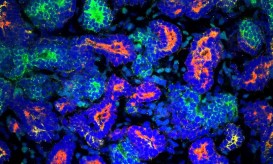

Μια σπουδαία εξέλιξη στον τομέα των μεταμοσχεύσεων ανακοίνωσαν επιστήμονες από την Αυστραλία και την Ολλανδία χθες, Τετάρτη. Σύμφωνα με...